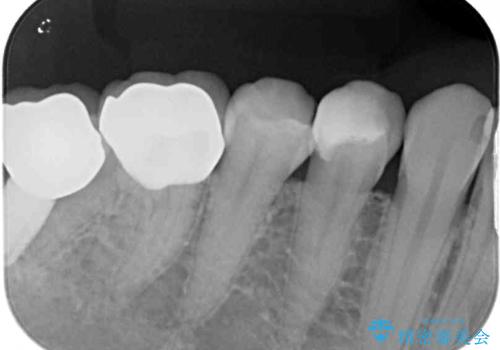

- 冷たいものがしみるとのことで来院された患者様です。

診査を行った結果、第一小臼歯にある樹脂の詰め物(コンポジットレジン)と歯の境目が痛みの原因であることが分かりました。

また、隣接する第二小臼歯も虫歯になっていることも分かったため、2歯を同時に治療するにしました。

下顎の目立つ位置であるため、セラミックインレーによる修復治療を行うこととしました。